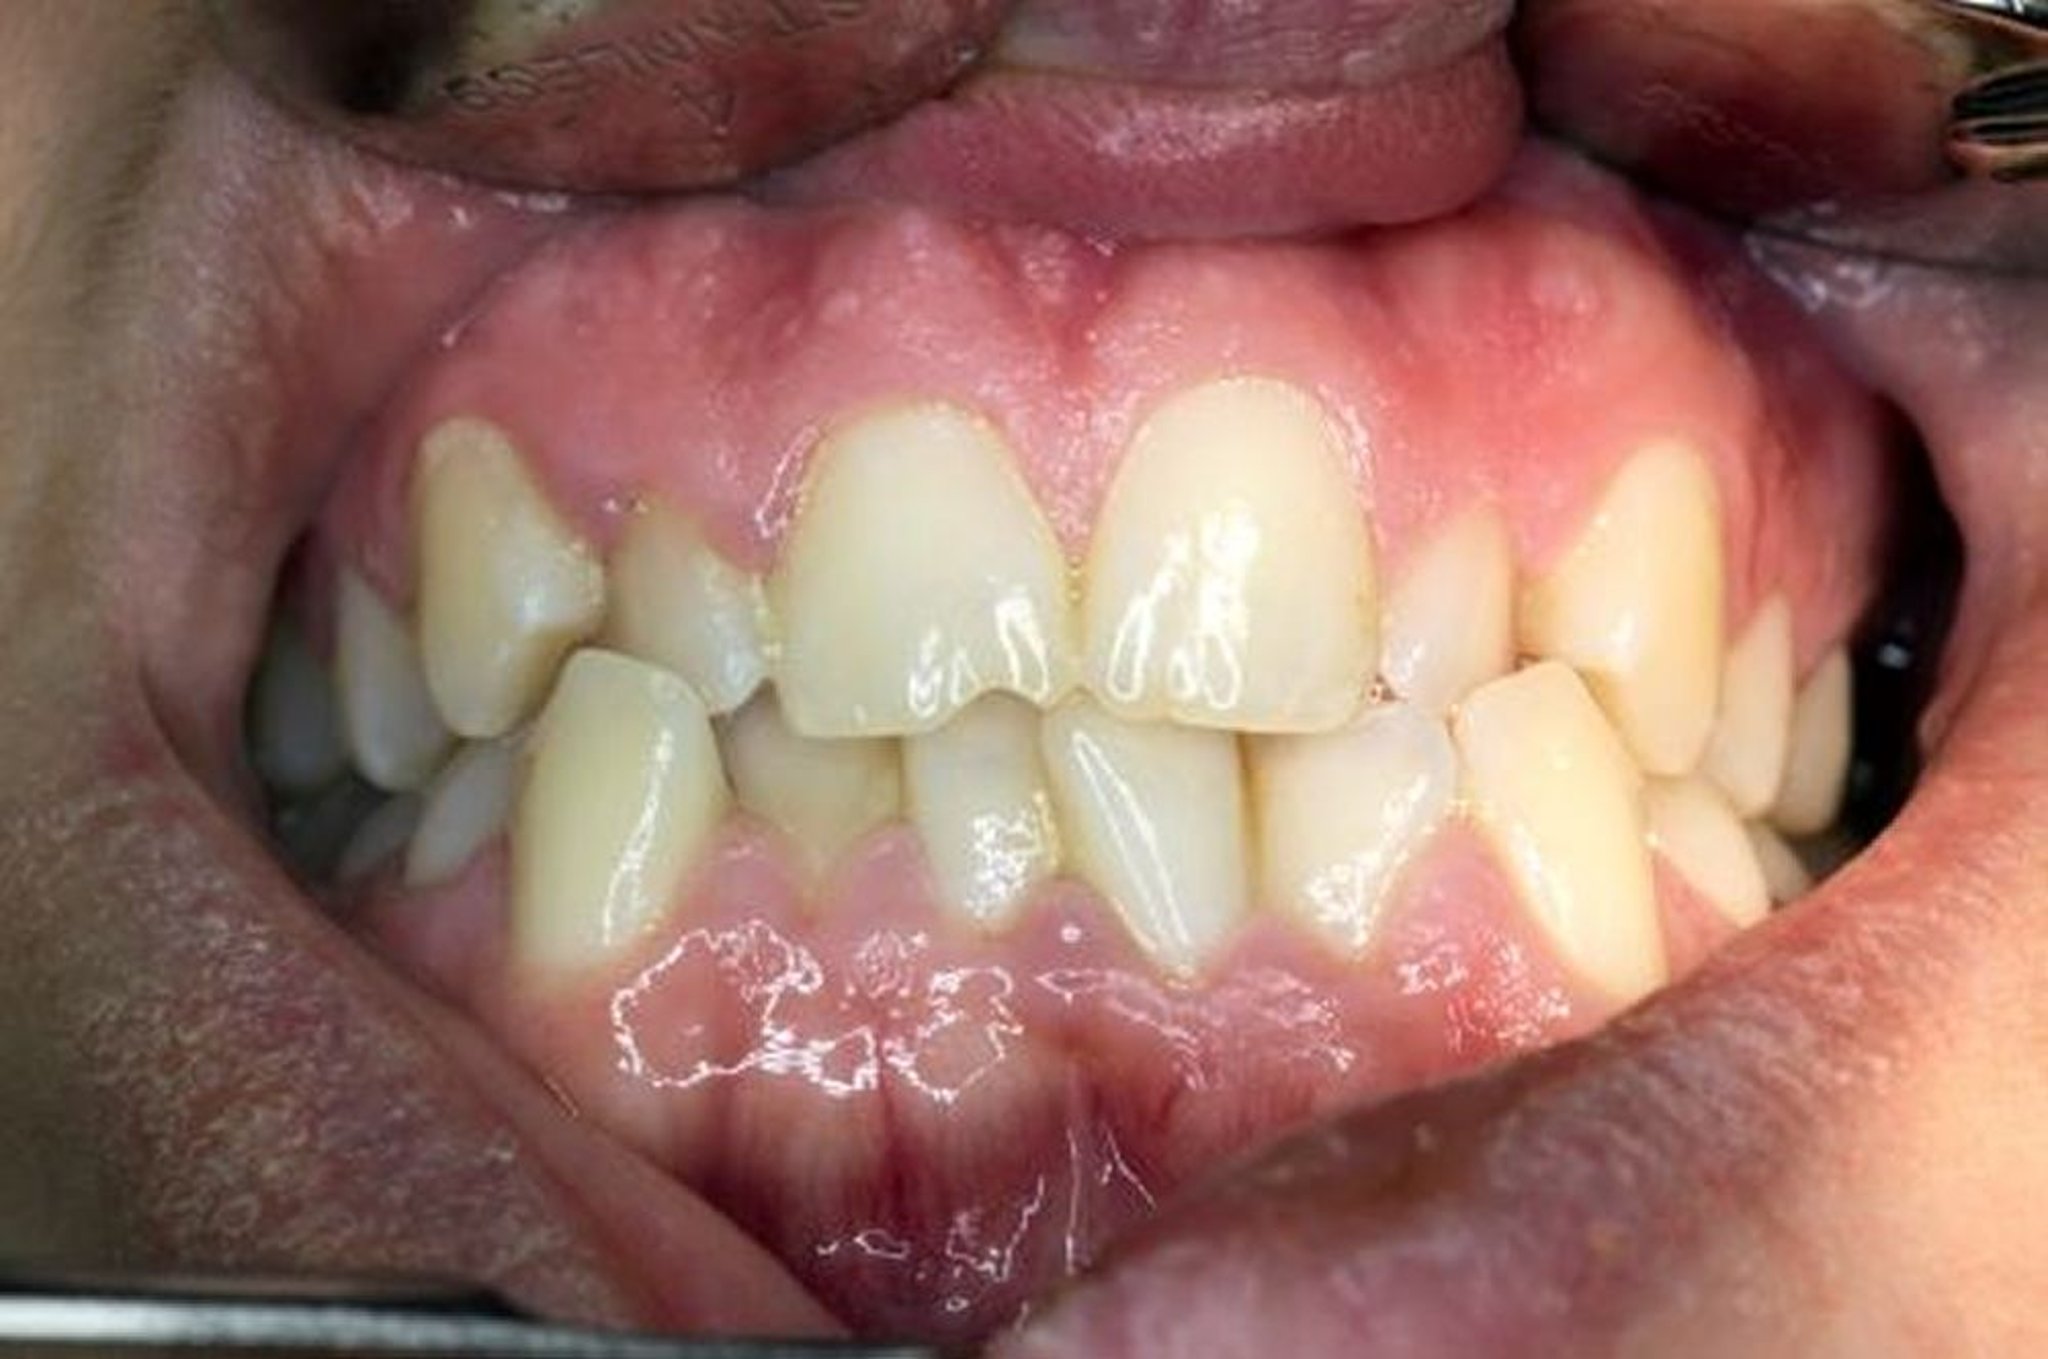

不正咬合(ふせいこうごう)とは、歯並びと上下の歯の噛み合わせが異常な状態のことです。

正常な場合は、上あごの歯が下あごの歯の外側にわずかにかぶさります。こうしてかぶさることで、それぞれの歯の突起(咬頭)が反対側の歯の対応するへこみにはまります。適切な歯並びは、最も効果的な咀嚼(そしゃく)に役立ち、さらに噛む力を均等に配分します。咀嚼では、大臼歯に約68キログラム(1000キロパスカル)の力がかかり、夜間の歯の噛みしめでは約110キログラム(1700キロパスカル)の力がかかります。不正咬合によって力が均等に配分されない場合、歯が異常にすり減ったり、歯冠の一部が破折したり、最終的には歯を喪失したりすることがあります。